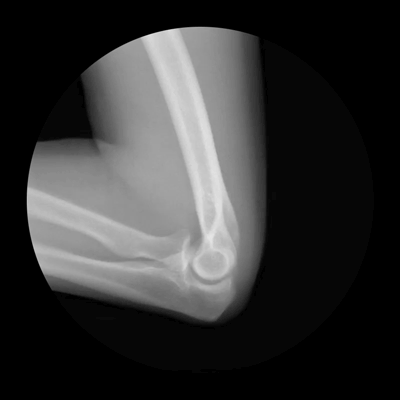

Cameron Drake put together sequences of x-rays into animated gifs that show human bones as they move inside our bodies. He says it’s for a website he’s working on. They are, definitely, cool!

(Images credit: Cameron Drake)